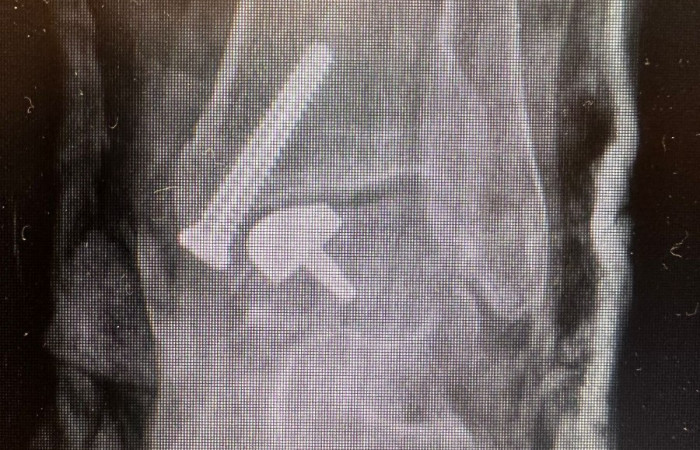

Implant custom-made

- Był to implant opracowany i dedykowany dla danego Pacjenta. Można powiedzieć, że „szyty dla niego na miarę”, na podstawie wykonanych wcześniej badań obrazowych TK i MR. Dzięki temu można było dokładnie odwzorować kształt prawidłowej budowy anatomicznej tego pacjenta, co pozwoliło na optymalne dopasowanie implantu. W efekcie przełoży się to na lepszy wynik kliniczny i trwałość elementu – tłumaczy dr hab. Henryk Liszka.

- Zabieg ten był pewnym rodzajem artroplastyki, ponieważ wszczepialiśmy coś sztucznego, natomiast był niezmiernie mało inwazyjny, ponieważ nie zastępowaliśmy całego stawu, tylko naprawialiśmy lokalne uszkodzenie. Tłumacząc to obrazowo – to tak jakby zrobić plombę w zębie, zamiast zakładać cała koronę. A do tego wszystko custom-made – mówi dr hab. Liszka.